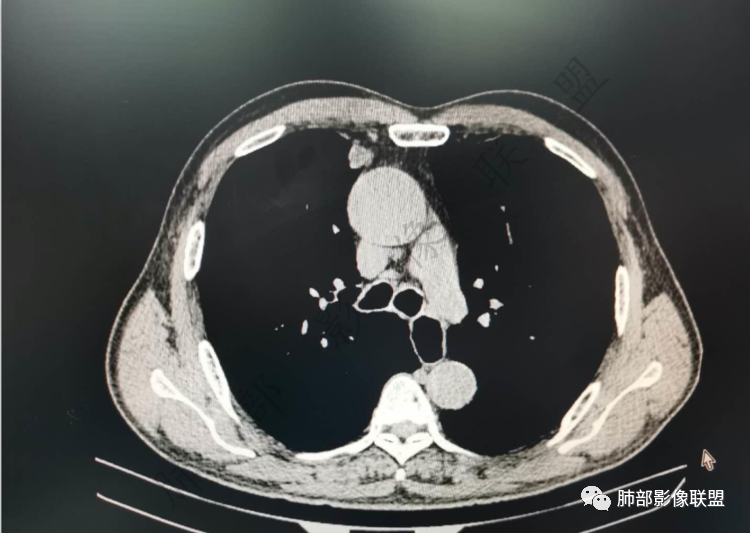

实性有隆起的小结节,内部有坏死、周围包括内乳动脉有增粗

右肺上叶前段胸膜下结节,边缘分叶毛刺,血管集束,支气管截断,纵膈胸膜牵拉,内乳动脉增粗,密度不均,中央可见坏死,两个月短期随访结节有增大,考虑恶性,腺癌。鉴别结核。

肺气肿背景,右肺上叶纵隔旁胸膜下结节,有血管集束,支气管堵塞,内乳动脉增粗,增强不均匀强化,内可见低密度区。考虑为恶性可能性大

右肺上叶前段胸膜下结节,近段支气管截断,血管伸入结节内,密度不均,同侧临近内乳动脉增粗,不均匀强化,肺气肿背景,两月明显增大,考虑低分化鳞癌,隐球菌代排

老年男性,白细胞计数及CRP稍高,右肺上叶结节,两个月来有增大,部分边缘可见边界模糊的GGO,局部边缘平直、凹陷,临近胸膜增厚,内见坏死,坏死区边界未见明显壁结节,壁较厚而且均匀强化,支气管似乎有扩张然后截断,近端血管增粗明显。考虑炎性病变,脓肿?有结核病人密切接触史,注意是否为结核。有点难以理解的是为什么右侧内乳动脉增粗明显。

内乳动脉关系似乎不密切